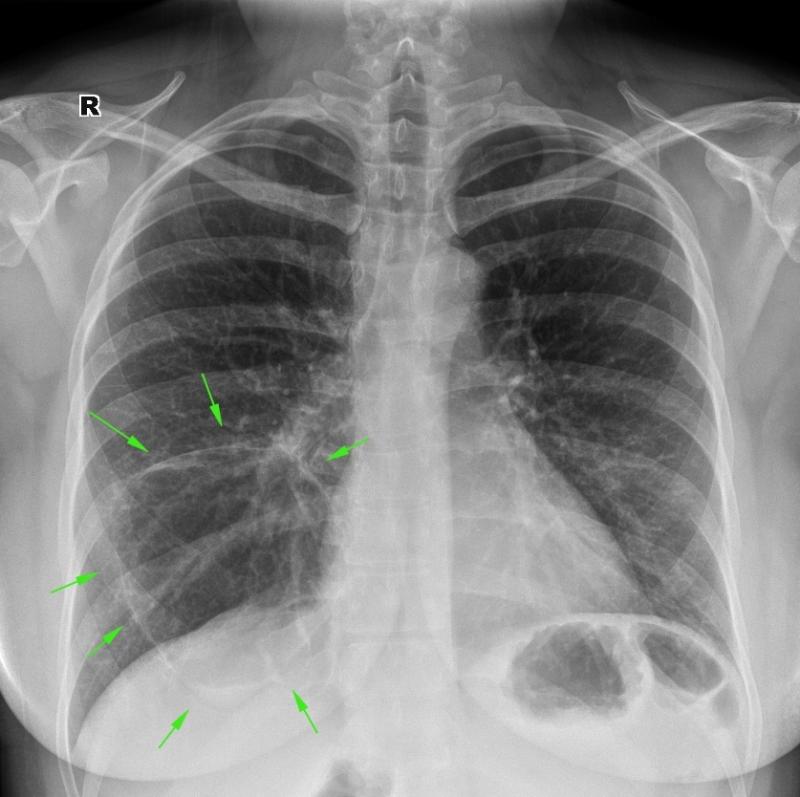

Рентгеновские снимки при пневмоцистной пневмонии